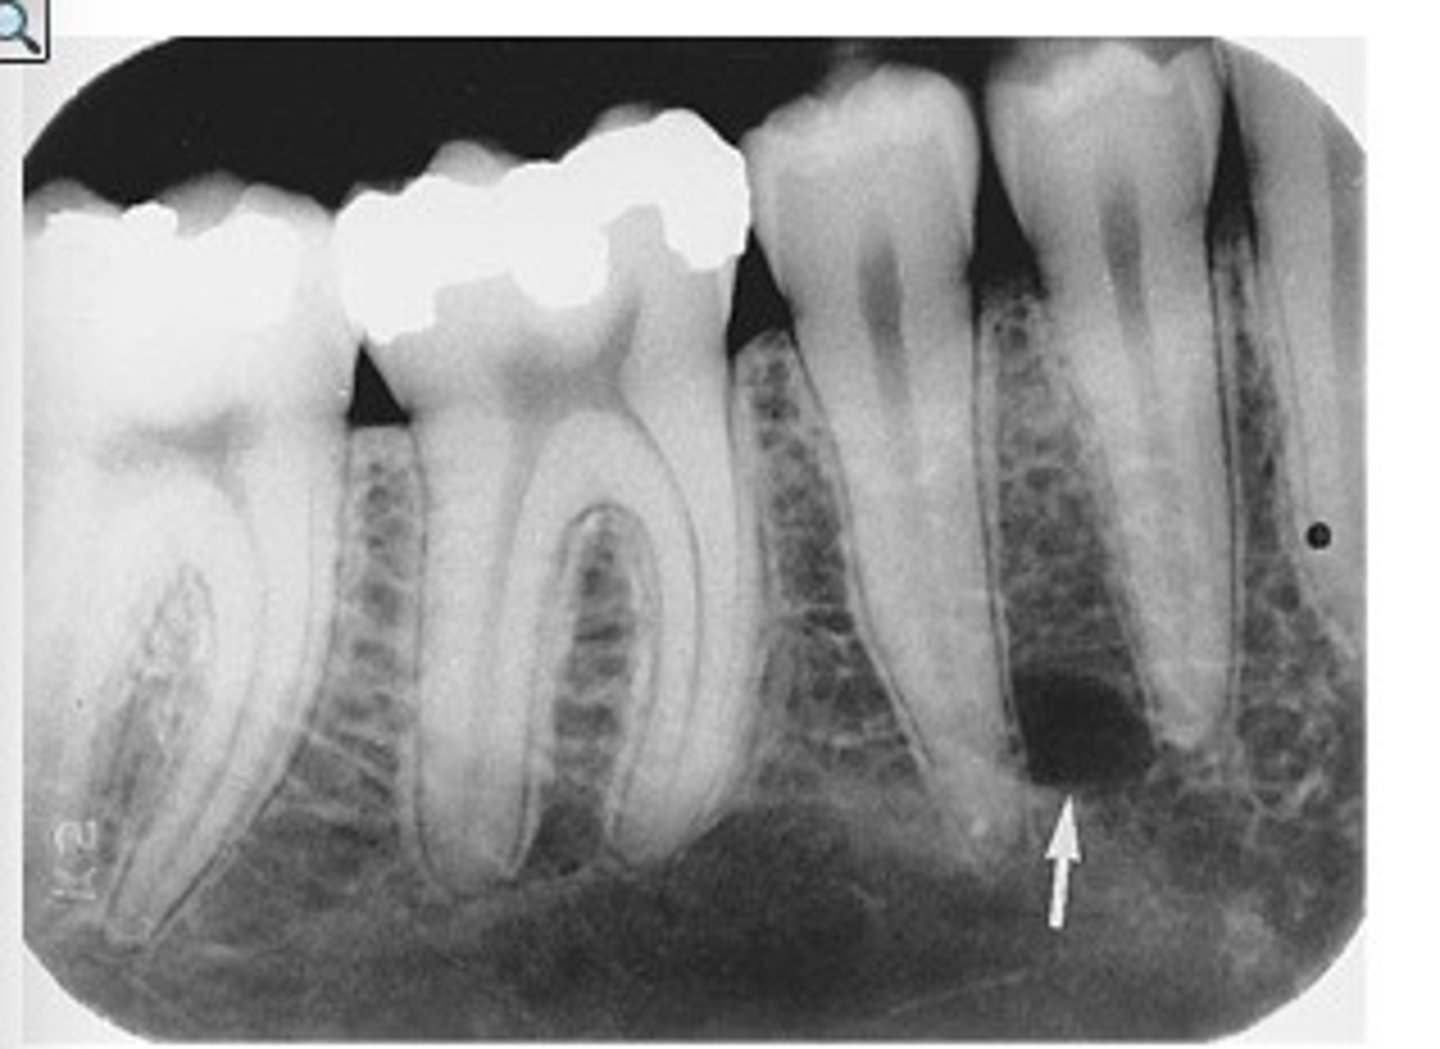

what is this?

what is this radiolucent area in the image?